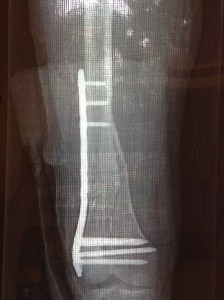

Needless to say I was somewhat anxious about the level of medical care that might be available but once we got into the hospital and they started to assess my injury, I could tell that I was receiving the same standard of care that one would expect in any of the major Melbourne hospitals. A set of X-rays and an MRI scan confirmed a very nasty fractured femur from my knee to about half way up my thigh, where the bone had shattered into a number of fragments. After a fair bit of “too-ing and fro-ing” about payment (which involved Phil having to come back into the hospital at midnight), I had surgery to insert a plate and screws very early the following morning. I had a short stay in hospital (fabulous nursing care) and was discharged the next day with an enormously swollen leg, crutches, a swag of medication and orders to not put any weight on my leg for one month.

Since arriving back, I have been staying with Leonie in Melbourne, and spending weekends with our son Reece and his girlfriend in Geelong. My leg has again been x-rayed and my orthopaedic surgeon has reviewed it and advised that I need to be non-weight bearing on crutches for 3 months until there is sufficient new bone formed around the fragments to hold my weight. A bit of a drag, but more importantly this has created an accommodation crisis as our apartment in Melbourne is up three flights of stairs and there is no lift in the building. Our friends and family have been fantastic and we have had a number of offers, so we just need to work out the best option for everyone.